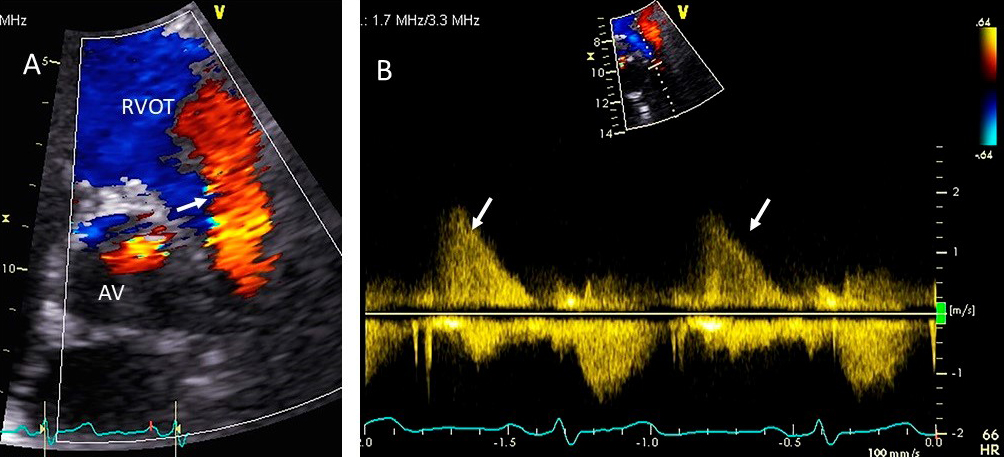

These criteria are generally more reliable in central jets. Pulmonary artery systolic pressure, mitral inflow E wave velocity and pulmonary vein flow pattern are other helpful parameters. Systolic pulmonary vein reversal (Fig. 1) is highly specific for severe MR but is not very sensitive. Discrepancy may occur between MR ERO and RV in mitral valve prolapse in early stages of MR where non holosystolic MR jet duration and hence regurgitant volume are smaller than the PISA derived EROA which does not account for the duration of MR jet. 2D vena contracta width may be unreliable in eccentric jets, however direct measurement of regurgitant orifice can be done using 3D color Doppler vena contracta area which may allow better quantitation of MR in central as well as eccentric MR jets [5] as well as in patients with multiple MR jets in whom PISA quantitation by adding multiple jets has not be validated and in whom continuity equation cannot be performed [6].

Fig. 1.Degenerative MR due to Flail posterior mitral valve leaflet. (A) TEE 4 chamber view showing a flail posterior mitral valve resulting in a severe anteriorly directed mitral regurgitation jet. LA, left atrium; LV, left ventricle; AML, anterior mitral leaflet; PML, posterior mitral leaflet. (B) TEE 4 chamber view color Doppler showing anteriorly directed mitral regurgitation with PISA (red arrow). AML, anterior mitral leaflet; AV, aortic valve. (C) Pulsed wave Doppler showing left upper pulmonary vein systolic flow reversal. (D) 3D TEE enface view of the mitral valve from the atrial perspective demonstrating P2 flail scallop with torn chordae. Aortic valve is a 9 o’clock position. AML, anterior mitral leaflet; PML, posterior mitral leaflet.